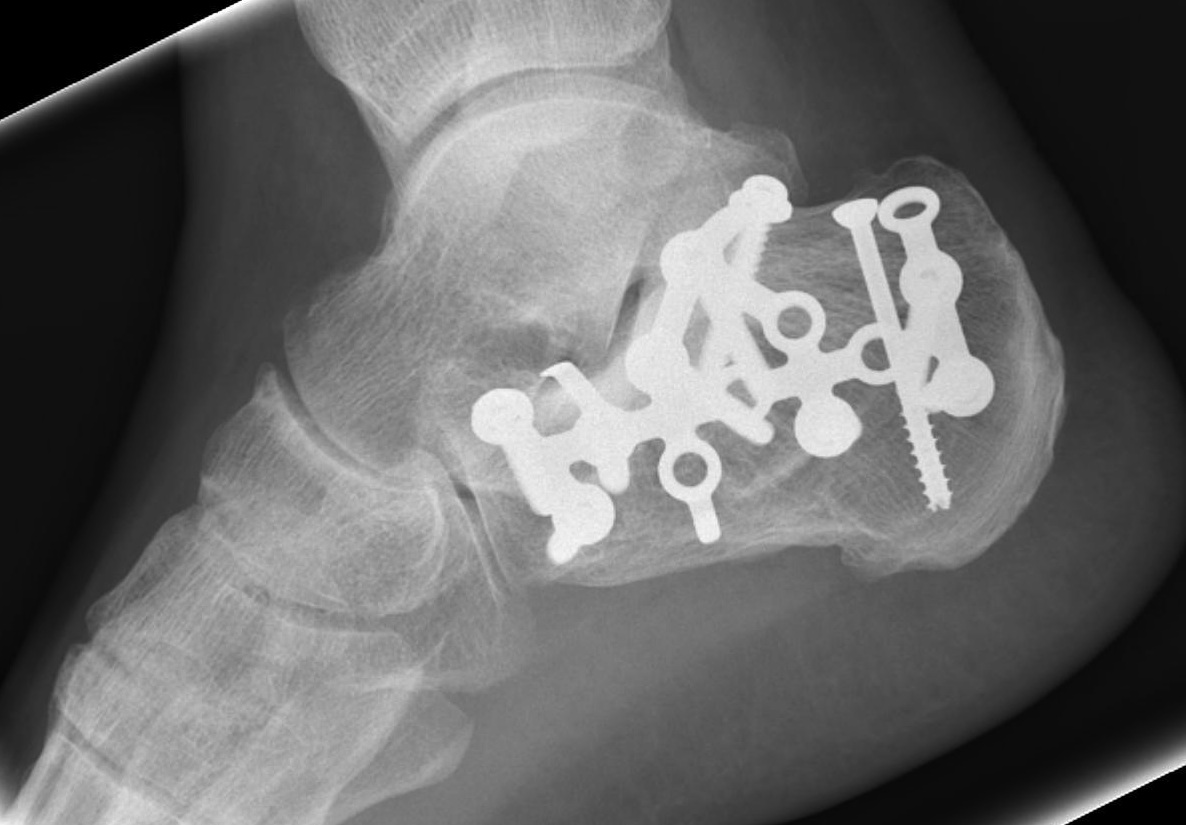

ORIF lateral plate using extensile lateral approach

Depuy Synthes calcaneal locking plates PDF

Technique

AO surgery reference extensile lateral approach

AO surgery calcaneal ORIF lateral plate

Extensile lateral approach

- vertical limb: between tendoachilles and fibula

- horizontal limb: in line with 5th metatarsal towards CC joint

- full thickness flaps - care ++++ with apex of incision

- divide peroneal retinaculum

- peroneal tendons elevated

K wires to retract skin flap

- 2 in talus / 1 in fibula

Expose subtalar joint

Reduction of varus

- Steinmann pin into tuberosity

- can elevate and pull out of varus

Reduction of subtalar joint

- open lateral wall fragment to access to subtalar joint

- lamina spreader

- reduce and ORIF with screws

- reduce and ORIF sustentaculum fragment

Anatomical contoured locking plate